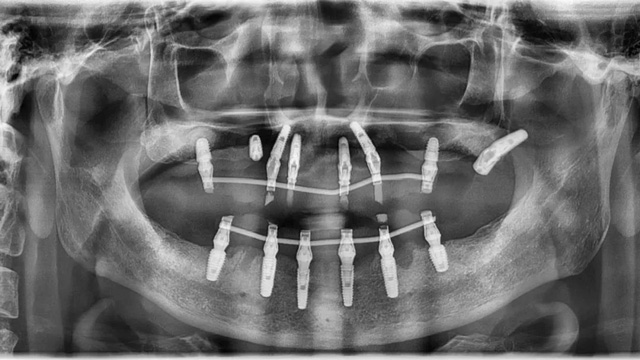

由于王先生在上一家診所種下的6顆種植體比較短小,在力學(xué)方面達(dá)不到修復(fù)標(biāo)準(zhǔn),還有兩顆因?yàn)樗蓜?dòng)和頸部暴露無法使用,李陽軍醫(yī)生又加種了3顆更長更粗的,以確保長期穩(wěn)定性。由于骨量不足,有兩顆采用了傾斜植入以增加骨接觸的面積,目的也是為了更加穩(wěn)固,還有一顆因?yàn)樵恢霉橇刻?,改為在其他位置種植,采取了高難度的術(shù)式。

據(jù)李陽軍醫(yī)生介紹,對(duì)比檢查報(bào)告可以看到,王先生的骨量和牙周條件比2021年時(shí)差了很多,治療難度顯著增加。不僅如此,他因?yàn)橹暗闹委煼桨覆焕硐牒蛢深w種植體無法使用,最后承擔(dān)了更多的種植費(fèi)用,也承受了更長的缺牙期。

“他如果21年就種植,對(duì)患者對(duì)醫(yī)生來說都要簡單得多,早就戴上牙用了幾年了!”